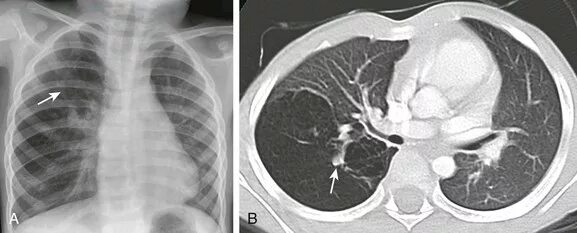

Утолщение бронха